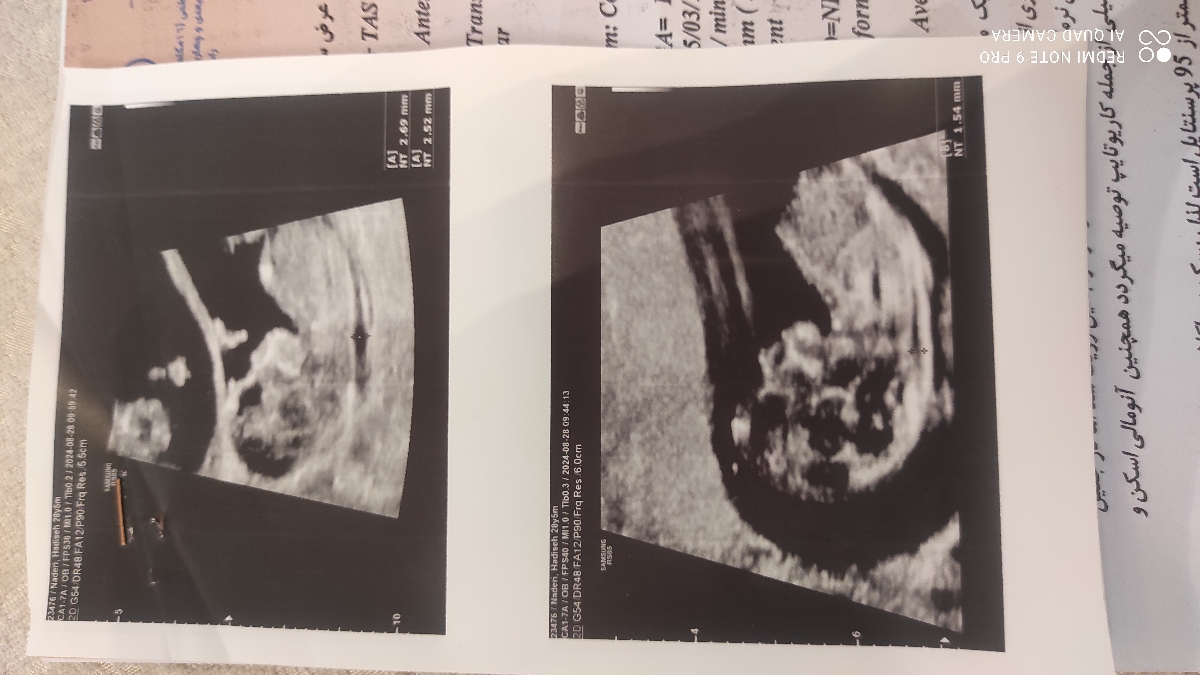

بنده بارداری دوقلویی هستم

و طبق انتی من ۱۱هفته و ۴ روزم هست

اما متاسفانه یکی از قل ها آن تی مشکوک دارد ممنون میشم تفسیر و راهنماییم کنید

سلام خانم دکتر لطفاً بهم بگید nt قل اول من مشکوک هست؟

پزشک اوما

سلام به روی ماهتون مامان جان

نگران نباشید عزیزجانم عدد ان تی زیر 3 خوب است و مشکلی ندارد، آزمایش خون غربالگری که آماده شد همینجا ارسال کنید تا ببینم